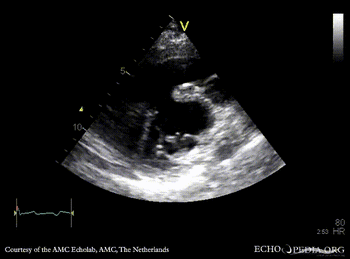

| PLAX: AVSD